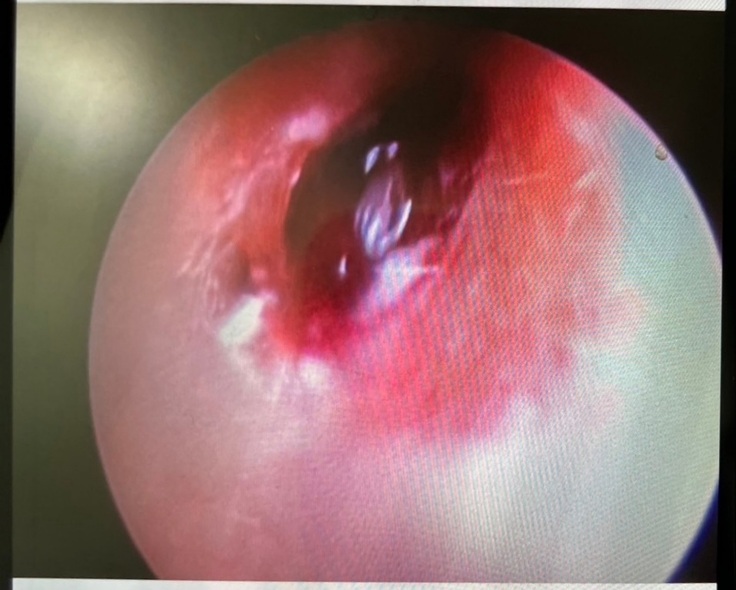

手術の結果としては外耳に腫瘍がありそちらを少しずつ取り除いていただきました。

一枚目は手術前、2枚目は切除あと。

ただ問題は鼓膜近くの見えている外耳の腫瘍ではなく、その先。つまり鼓膜の中、中耳の鼓室から腫瘍が派生していると思われるとのこと。

鼓膜を破っての腫瘍の派生とのこと。

幸いこの腫瘍は良性が多いということですが確認の為、病理検査に出すことになりました。

腫瘍が派生していると考えられる鼓室は汚れているのがCTで分かりました。